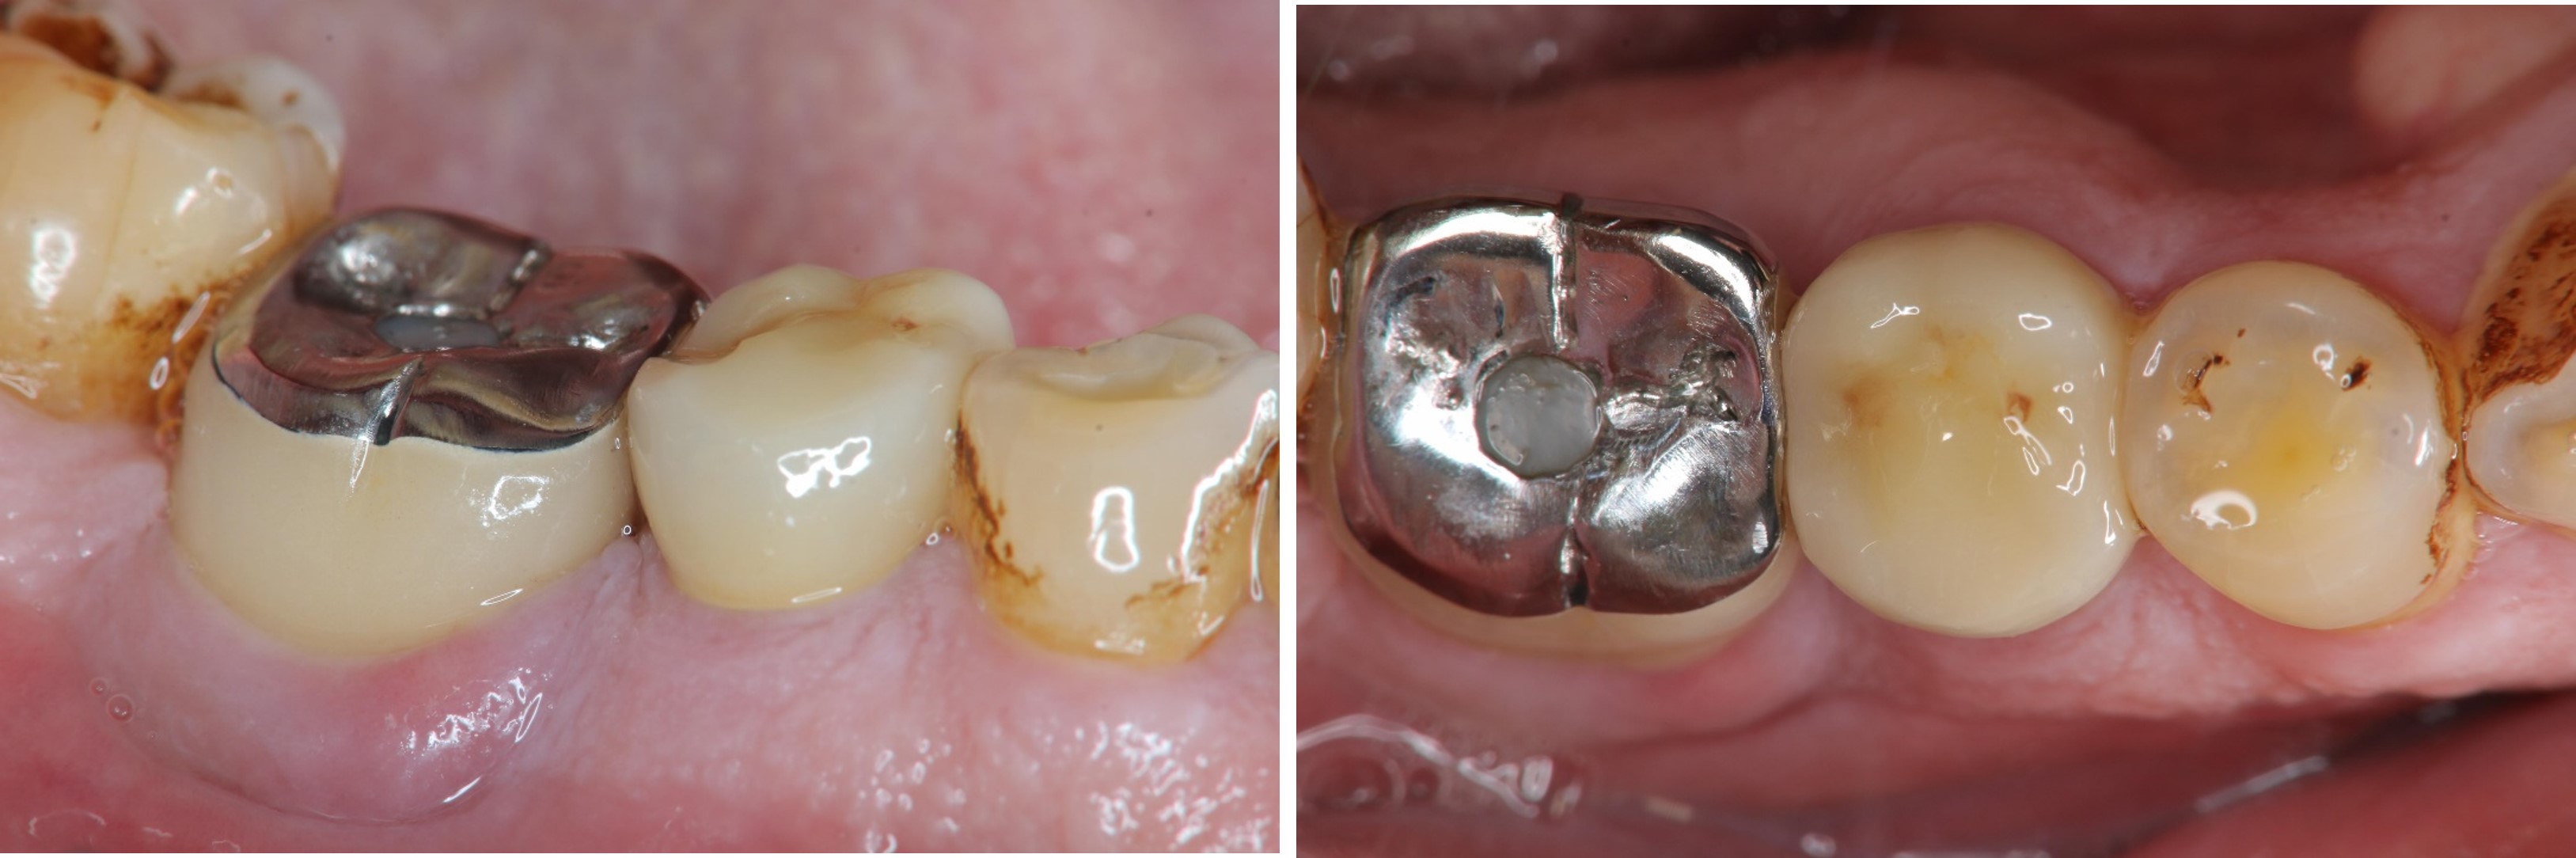

治療前#45蛀牙至牙髓

磨損與蛀牙,塞食物

術前、術後比較